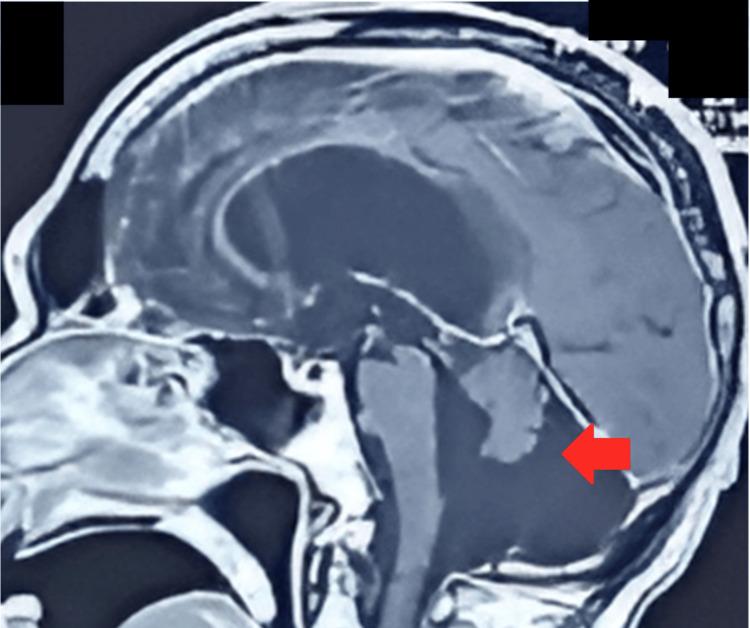

Dandy-Walker malformation is the most prevalent posterior fossa anomaly. Dandy-Walker variant, or Dandy-Walker complex, are terms devised to contrast those conditions that do not meet the standard of Dandy-Walker malformation. Dandy-Walker malformation is usually a congenital diagnosis. Our case calls attention to an extraordinary presentation of Dandy-Walker malformation in adulthood. A 76-year-old male patient initially presented to the Emergency Department at Dow University Hospital at Ojha Campus on the grounds of suspicion of a respiratory infection. COVID-19 was suspected; however, polymerase chain reaction (PCR) testing yielded a negative result. The patient later developed an erythematous and swollen left arm, which pointed towards a diagnosis of cellulitis, and the patient was managed accordingly. After being moved to the General Medicine Ward, our team noted that the patient was bed-bound and conducted a neurological exam, in which he presented with incoordination, less brisk and pendular deep tendon reflexes, and hypotonia in lower limbs, all suggestive of cerebellar involvement. The patient was also lethargic and was in a state of confusion, suggesting an altered mental status. Subsequent labs were completed, and bacterial pneumonia was confirmed on pleural fluid analysis. A CT scan of the head and an MRI scan of the brain were also ordered to investigate the reason for neurological involvement. The imaging displayed hallmarks signifying Dandy-Walker malformation, such as enlargement of the fourth ventricle, hypoplastic vermis, and posterior fossa anomalies.

丹迪-沃克畸形是最常见的后颅窝异常。丹迪-沃克变异型或丹迪-沃克复合体是为了与那些不符合丹迪-沃克畸形标准的情况相区分而设计的术语。丹迪-沃克畸形通常是一种先天性诊断。我们的病例提醒人们注意丹迪-沃克畸形在成年期的一种特殊表现。一名76岁男性患者最初因疑似呼吸道感染被送往奥贾校区的道大学医院急诊科。怀疑感染了新冠病毒;然而,聚合酶链反应(PCR)检测结果为阴性。患者后来左臂出现红斑和肿胀,这表明诊断为蜂窝织炎,并对患者进行了相应治疗。转至普通内科病房后,我们的团队注意到患者卧床不起,并进行了神经系统检查,检查发现他存在共济失调、深部腱反射减弱且呈摆动样、下肢肌张力减退,所有这些都提示小脑受累。患者还嗜睡且处于意识模糊状态,提示精神状态改变。随后完成了各项实验室检查,胸腔积液分析确诊为细菌性肺炎。还安排了头部CT扫描和脑部MRI扫描以调查神经系统受累的原因。影像学检查显示出表明丹迪-沃克畸形的特征,如第四脑室扩大、小脑蚓部发育不全和后颅窝异常。